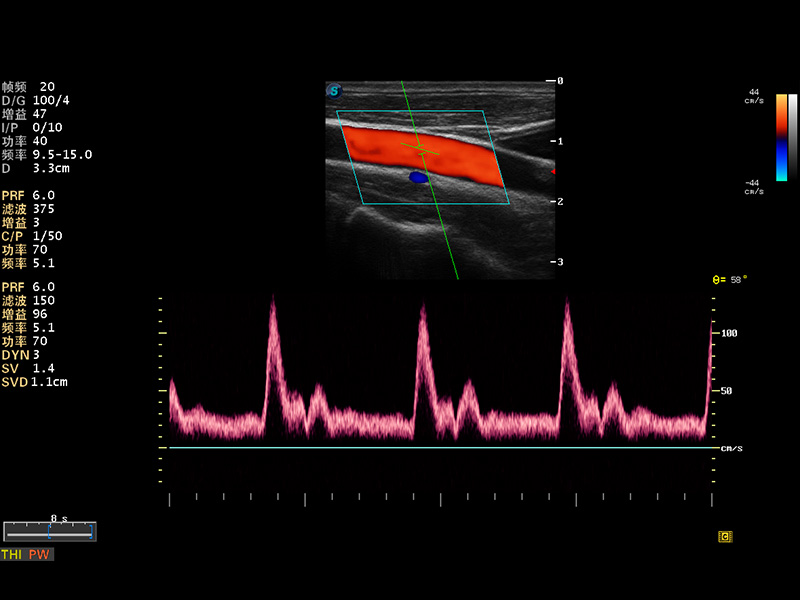

S8 EXP便携式彩色多普勒超声诊断仪是环球UG官网研发的高端全身应用型便携彩超。高通道的VIS平台融合可视化(Visual)、智能化(Intelligent)和人性化(Smart)的特点,配以环球UG官网自主研发生产的探头大家族,使您能够快速、准确的获得病人信息,提高工作效率的同时减轻疲劳。

成像技术

多波束形成器

μ-Scan微米成像

谐波成像

实时宽景成像

空间复合成像

3D/4D成像